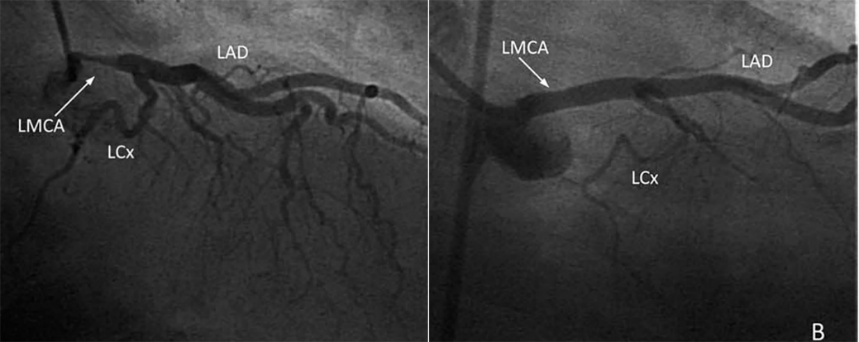

图2 左冠痉挛表现为冠脉细长

冠脉弥漫性痉挛会出现2种情况:基本正常冠脉发生弥漫性痉挛表现为基本正常的光滑的细长冠脉(如前所述);不均匀斑块基础上发生的弥漫性痉挛则表现为程度不一的弥漫性狭窄,容易和严重斑块导致的弥漫性病变相混淆。

仔细观察,尽管痉挛性弥漫性狭窄的程度不尽一致,但总体基调还是“光滑和对称”(图3),和斑块性狭窄有所不同。